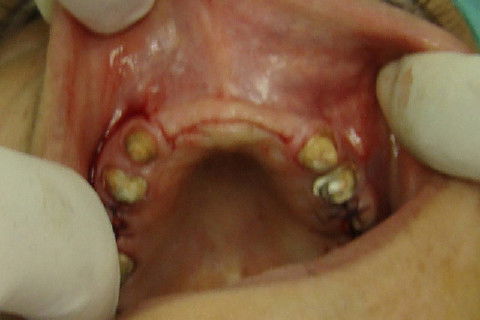

Aspecto clinico da região anterior maxilar, após remoção das proteses antigas